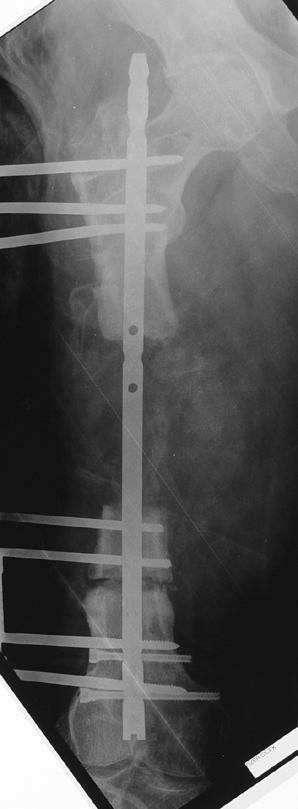

Uygun radikal debridman tüm nekrotik kemik ve yumuşak dokuların çıkartılmasını gerektirir, ve sıklıkla uzuvda instabiliteye neden olur. Kalan kemik ve yumuşak doku defektinin bir şekilde fiksasyonu ve rekonstrüksiyonu gereklidir. İlizarov’un ortaya koyduğu distraksiyon osteogenezi yöntemi, kaynamanın elde edilmesi, deformitenin düzeltilmesi, bacak boy eşitsizliğinin giderilmesi ve segmental defektlerin rekonstrükte edilmesi için başarıyla kullanılmaktadır.

Eksternal fiksatör ile geçen süre (eksternal fiksasyon indeksi), gereken distraksiyon miktarına bağlıdır ve bu süre boyunca bazı komplikasyonlarla karşılaşılabilir. Distraksiyon dönemi sona erdikten sonra, distraksiyon süresinin iki katını aşan konsolidasyon döneminde hastalar eksternal fiksatörü zorlukla tolere edebilirler. Yeterli konsolidasyon sağlanmadan eksternal fiksatör çıkartılırsa ise kırıklar, deformite ve kısalık oluşabilir. Hastanın fiksatör ile birlikte geçirdiği sürenin azaltılması ve böylece hasta konforunun ve aktivite düzeyinin arttırılması için intramedüller çivi üzerinden uzatma yöntemi uygulanmaktadır. Bu yöntemde distraksiyon dönemi sona erdiğinde kemiğin içindeki çivi statik olarak kilitlenmekte ve eksternal fiksatör çıkartılmaktadır. Stabilizasyon intramedüller çivi tarafından sağlandıktan sonra konsolidasyon dönemi gerçekleşmektedir. Bu şekilde hem eksternal fiksatörün uzun süre kalmasından hem de erken çıkartılmasından kaynaklanan komplikasyonların önüne geçilmektedir.

Vaka 2